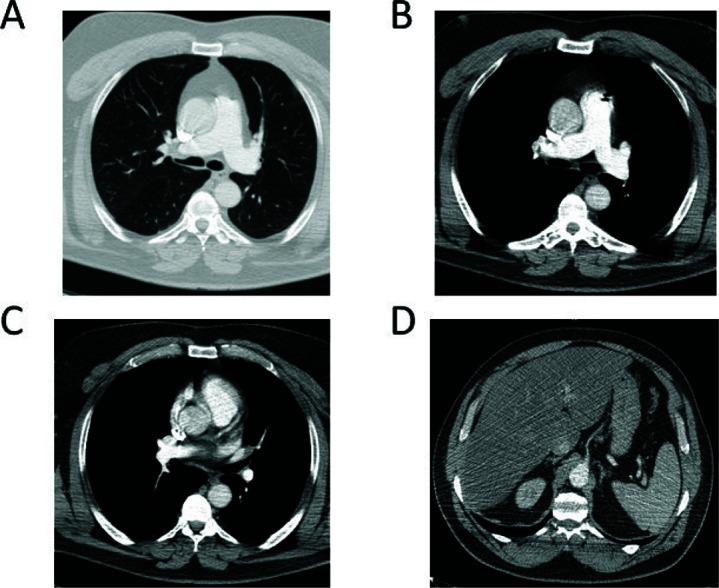

The advent of immunotherapy, and in particular the use of immune-checkpoint inhibitors, has profoundly revolutionized the treatment of different cancers, including lung cancer. The use of immune-checkpoint inhibitors has prolonged survival in lung cancer with a strong benefit in a significant percentage of patients with non-small-cell lung cancer. Here, a clinical case of a patient who, despite testing negative for PD-L1, displayed a sustained complete response to immunotherapy treatment in advanced metastatic non-small-cell lung cancer is presented. Additionally, recent findings concerning the application of immunotherapy in this context are reviewed.

Abstract Image